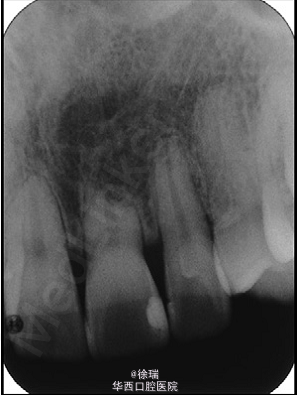

尖牙的异位萌出多见于上颌,可造成相邻牙齿的根尖吸收。最近遇到了一个病例,15岁的女孩儿,安氏III类,上颌尖牙阻生,因为尖牙的位置太过靠近侧切牙和中切牙根方,邻牙发生了严重的根尖吸收。那这样的病情又该如何矫正呢?